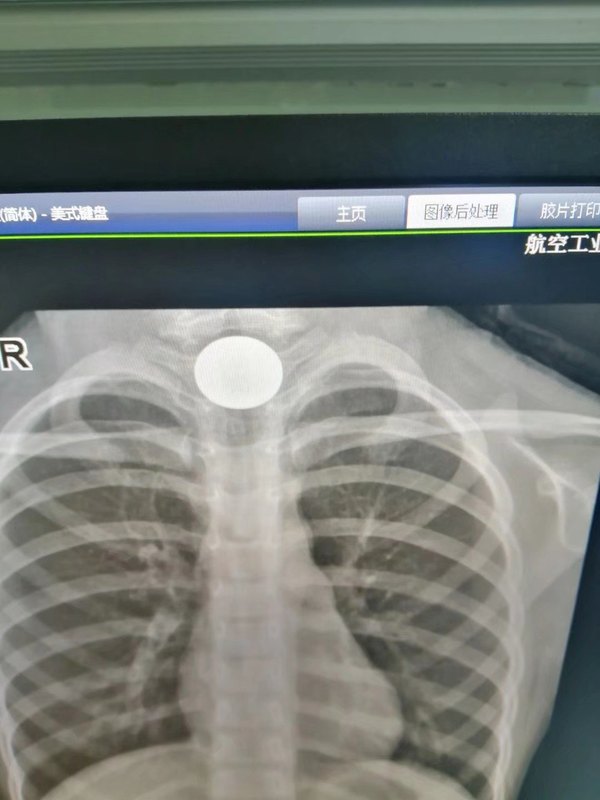

调皮的小孩,有的时候口腔容易含着硬币,一不小心吞了下去,掉在胃里问题不大。要是卡在食管,那就危险了。前几天一位7岁小女孩,误吞一元硬币半小时来我院耳鼻喉科就诊,患儿出现呼吸困难,难受的要命。襄阳364医院耳鼻喉科余胜朝主任马上在门诊双腔导尿管Foley法30秒内取出硬币,仅仅只花了三百多元。此法仅仅使用于卡在食管圆滑的东西硬币或者其他,如果有刺或者有伦角的东西卡在食管不能用此法,否则容易伤着食管。原理就是导尿管越过异物后再注水,通过膨大的头带出异物。此法操作简单,小孩不痛苦,不需要住院,价格低,取得快,家长很感激! 取出来的硬币!